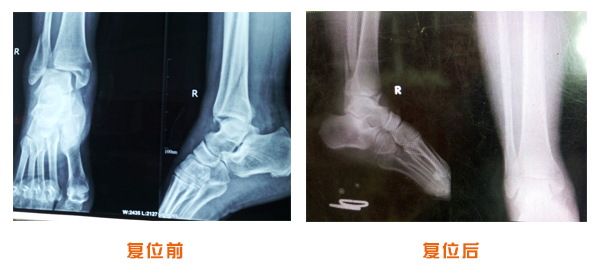

尺橈骨骨折治療前后